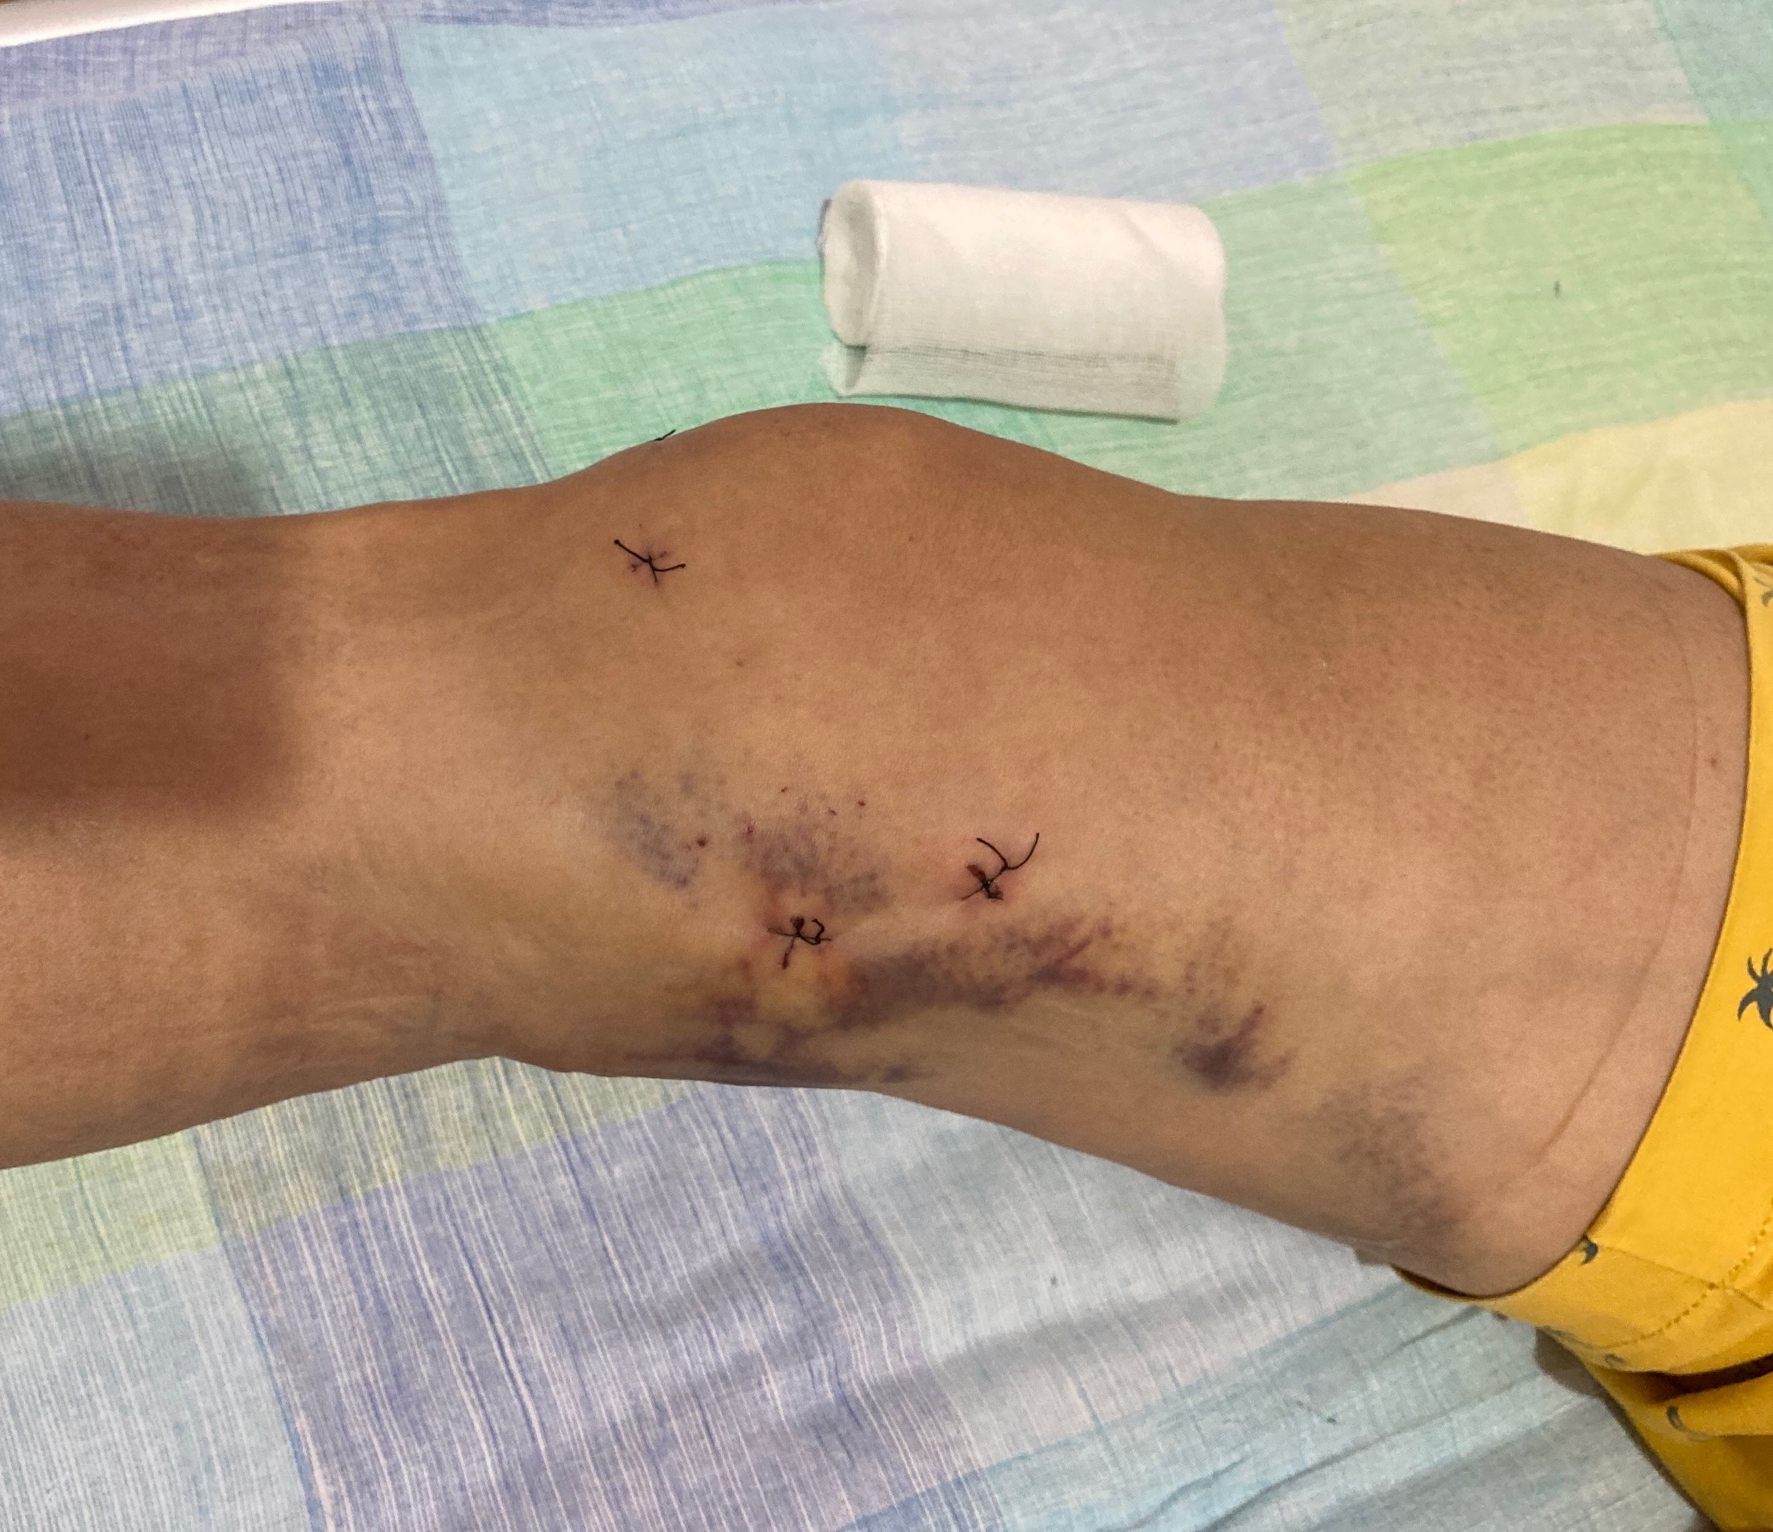

关节镜下腘窝囊肿微创切除术可从根本上解决以上难题,为腘窝囊肿的治疗开辟了新思路。优势在于:①内镜下处理关节内原发病变(半月板损伤、关节软骨退变、滑膜增生等);②直视下显露和切除囊肿,极大降低术后复发风险,同时还能够避免损伤腘窝后方神经和血管;③仅需在膝关节做3-4个不足1厘米的创口,手术创伤极小,术后当天下地正常活动,2-3天可出院,康复后疤痕不明显。

近日,崇州二医院骨三科成功实施一例全关节镜下腘窝囊肿切除术。患者经反复多次切开囊肿切除,术后复发,多次穿刺抽液均没有好转。患者来到二医院骨三科,经科室讨论后选择全镜下切除,手术方案为:采用双后内侧入路,内引流术+囊壁切除。手术施展顺利,目前患者恢复良好,囊肿完全消失。